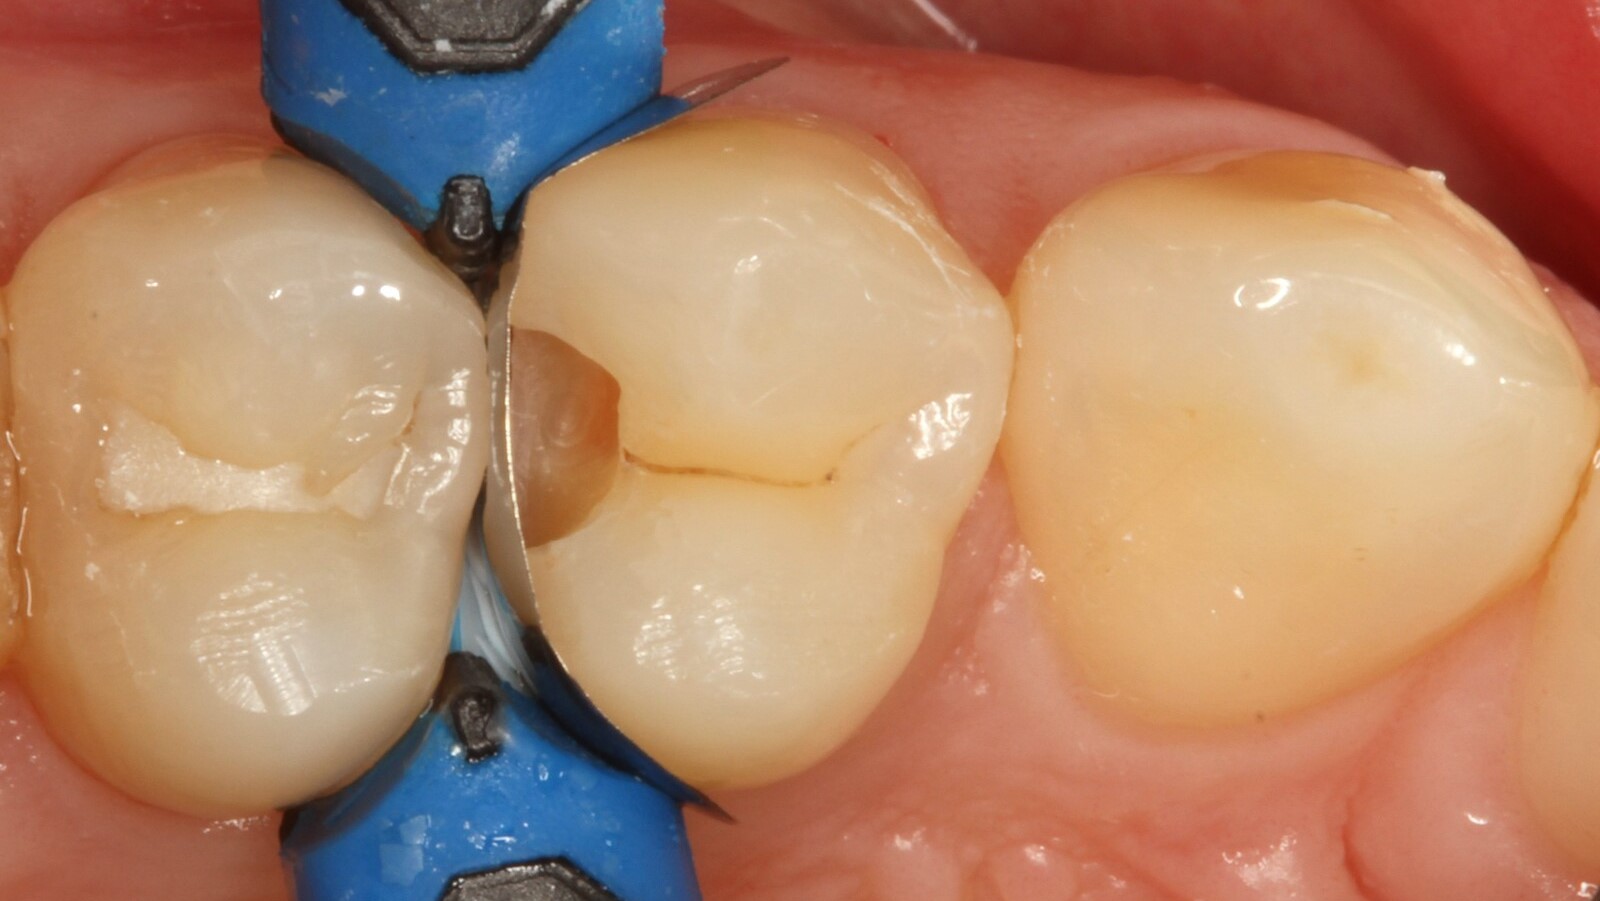

Professor Ernst identifizierte zunächst die versteckte Karies und öffnete die kariöse Läsion, um dem Patienten das Problem zu veranschaulichen (Abb. 1-2). Anschließend exkavierte er die Karies, präparierte die Kavität und setzte eine Teilmatrize ein (Abb. 3), bevor er die Kavität mit Adhäsiv versiegelte (Abb. 4). In einem einzigen Schritt füllte er die Kavität mit Venus Bulk Flow ONE (Abb. 5). Nach der Fertigstellung polierte Prof. Ernst die Restauration (Abb. 6) und fertigte ein Kontrollröntgenbild an, das ebenfalls die hervorragende Röntgenopazität von Venus Bulk Flow ONE zeigt (Abb. 7).